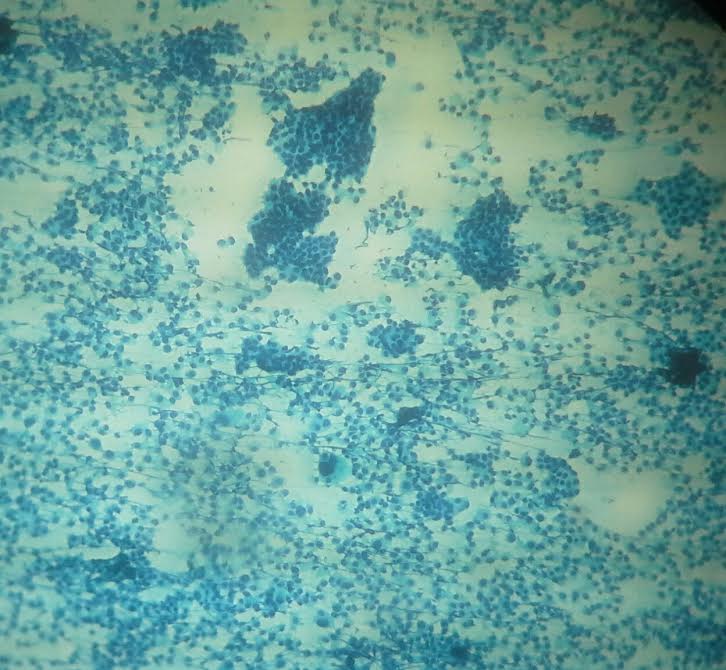

Cytology description

- Can use cellular pleomorphism, nuclear size, nuclear margin, nucleoli, lack of naked nuclei, cellular dyscohesion and mitoses in addition to necrosis to assess cytologic tumor grade, which correlates with histologic grade (Diagn Cytopathol 2003;29:185)

Cytology images